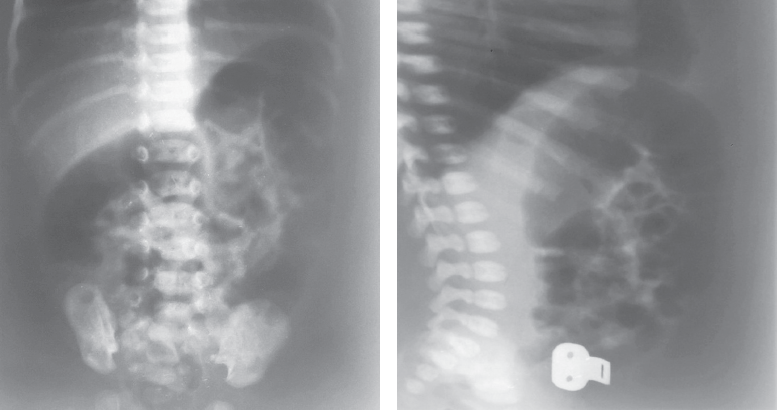

Болезнь Гиршпрунга, как правило, проявляется в первые дни жизни ребенка. Существование различных форм и вариантов ее проявления является основной причиной того, что у части пациентов заболевание не диагностируется в периоде новорожденности. C 2008 по 2019 г. в Детском городском многопрофильном клиническом специализированном центре высоких медицинских технологий г. Санкт-Петербурга находились на лечении 75 детей разного возраста с различными формами болезни Гиршпрунга. В 21 случае диагноз не был установлен сразу после рождения. У 11 новорожденных симптомы заболевания были неяркими и купировались сразу после опорожнения кишечника. У 2 детей с сопутствующей генетической патологией болезнь Гиршпрунга была заподозрена поздно, в связи с имеющимися особенностями опорожнения кишечника у этой группы больных. У части пациентов заболевание проявилось в виде стойкой задержки стула в более старшем возрасте. В статье приведены клинические примеры основных диагностических ошибок у пациентов с болезнью Гиршпрунга или подозрением на нее. Ошибки диагностики у детей раннего возраста связаны как с отсутствием хирургической настороженности у неонатологов родильных домов и отделений новорожденных, так и неправильной трактовкой клинической и рентгенологической картины. Дети в течение многих лет могут наблюдаться и лечиться у различных специалистов, прежде чем попадут в поле зрения детского хирурга.